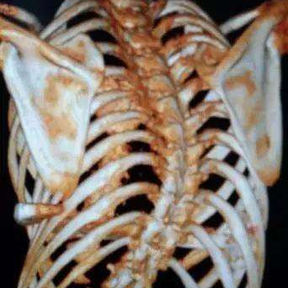

The patient was diagnosed with severe complex chest wall deformities accompanied by scoliosis. The heart was severely compressed and shifted to the left thoracic cavity.

We developed a personalized surgical plan for the patient. The operation first involved making incisions along the surgical scars on both sides of the chest wall to remove the bar inserted during the Nuss procedure. Then, a larger incision was made at the central scar on the anterior chest wall to fully expose the bone structure located at concave and convex areas of the chest wall. It was found that there were severe adhesions between the chest wall structure and the pericardium, with the heart being compressed into the left chest cavity.

​First, the adhesions were thoroughly released, and a portion of the protruding ribs and costal cartilage at the top of the protrusion was cut off. By lifting and pressing down, the chest wall was adjusted to its normal height. Second, three MatrixRIBs was used to replace the removed rib sections, and their curvature was carefully adjusted to closely resemble the normal curvature of the chest wall, thereby completing the reconstruction of the thoracic cage. Third, a bar was placed and flipped within the chest wall to elevate the most depressed part of the central chest wall. Lastly, two bars were placed on and secured to the bone surface of the lower half of the chest wall. The surgery achieved a satisfactory result, eliminating the deformities and restoring the chest wall to its normal shape.